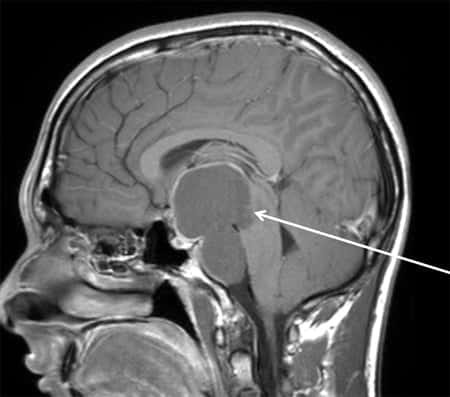

Рак верхних и нижних мочевыводящих путей — сложное онкологические заболевание, которое распространяется в почках и верхних мочевых путях. Рак мочевыводящих путей появляется в верхних мочевыводящих путях. К ним относят почечные чашечки, лоханки, а также мочеточники. Стенки данных органов выстланы несколькими слоями. К ним относятся слизистый, подслизистый, наружный соединительный и мышечный слои. Рак верхних мочевыводящих путей образуется непосредственно в поверхностном слизистом слое. Данный слой именуется уротелий, давая название заболеванию — уротелиальный рак верхних мочевыводящих путей.Читать далее